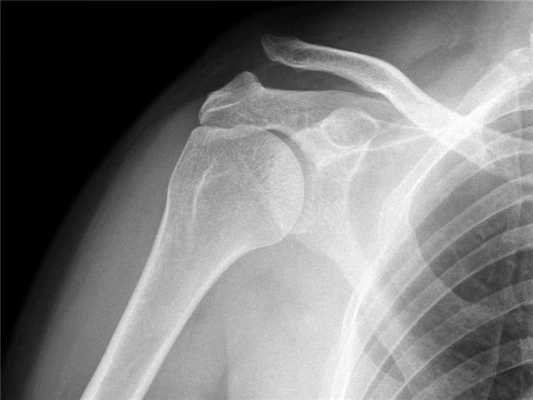

Поставить диагноз можно на основании рентгеновского снимка.

Для постановки диагноза и для определения степени повреждения акромиально-ключичного сочленения наиболее информативным методом исследования является рентген.

На рентгене при первой степени разрыва акромиально-ключичного сочленения будет видно расхождение между ключицей и акромионом.

При второй степени мы видим выступание ключицы над акромионом на расстояние не более половины ее диаметра.

При третьей степени ключица выступает над лопаткой на полный свой диаметр и даже более того.

На основании рентгена, при третьей степени повреждения, пациенту дополнительно назначается МРТ- это исследование позволит нам точно определить какие именно связки оказались разорваны, степень разрыва и поможет с выбором тактики хирургического лечения.

Практически во всех случаях определить получение вывиха ключицы оказывается достаточно легко, с учетом проявляемых клинических признаков. Из дополнительных методов исследования больному может быть назначено проведение рентгеновского исследования. Для правильного установления диагноза, целесообразно выполнять рентгенограмму здорового и больного плеча на одной пленке.

Диагноз вывиха акромиального конца ключицы иногда очень прост и все очевидно при осмотре, а иногда приходится решать целую головоломку. Наиболее оптимальным и распространенным способом диагностики является рентгенография. Стоит сказать, что, как не бывает одинаковых людей, так и не бывает одинаковых ключиц. Чаще всего причиной ложного диагноза индивидуальные особенности акромиально-ключичного сустава.

Поэтому целесообразно выполнять рентгенограмму не одного плеча, а двух сразу - что позволит оценить нормальное строение противоположной ключицы.

В сомнительных случаях иногда выполняют функциональную рентгенографию - в руку берут груз, который оттягивает ее вниз и вывих становится более очевидным.